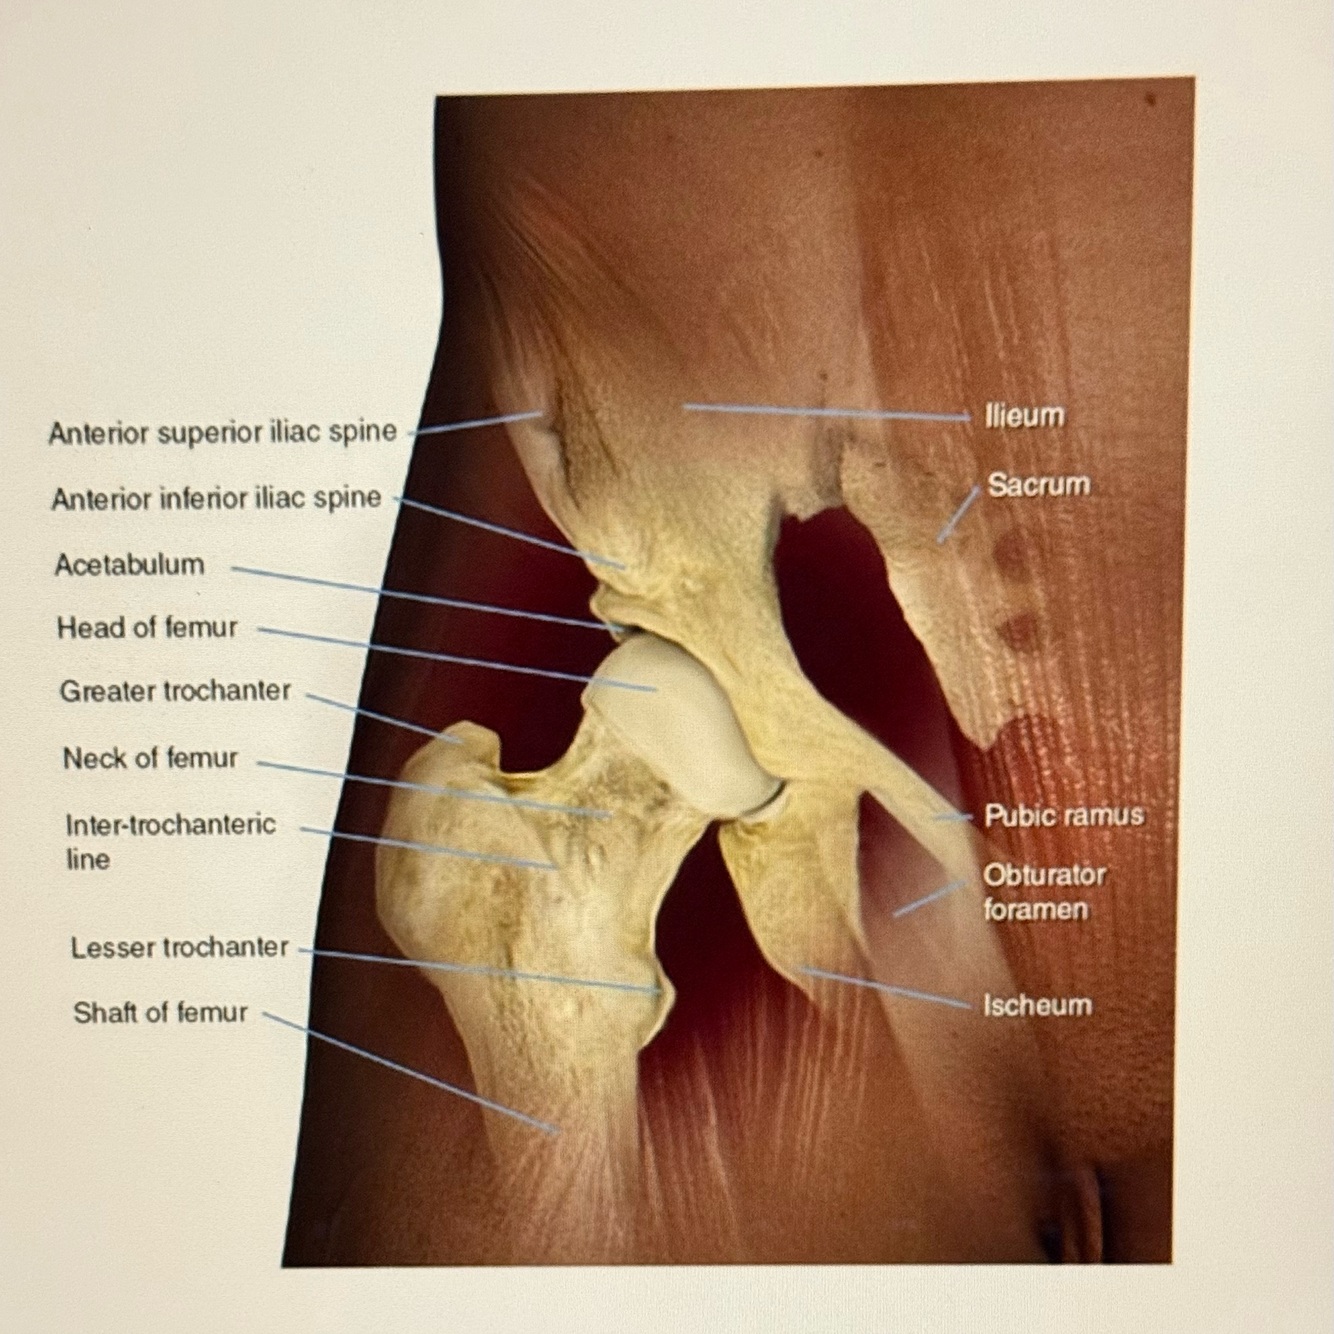

1

Q

Letter D points to

A

Acetabulum

2

Letter E points to the

Ischium

3

Letter G points to the

Superior pubic ramus